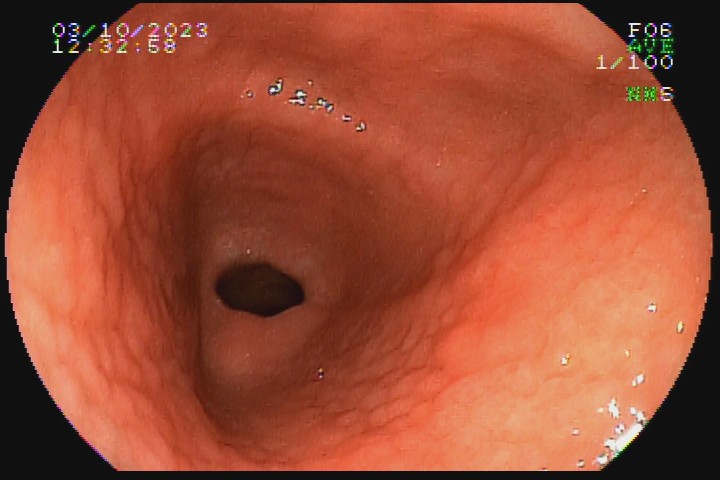

A gastrite por Helicobacter pylori é uma das formas mais comuns de gastrite. Apesar de o diagnóstico ser realizado por histologia, teste da urease, sorologia ou teste respiratório de ureia marcada, há sinais endoscópicos que possibilitam forte suspeita de positividade ou negatividade dessa infecção. Os sinais  de positividade são: enantema difuso, edema da mucosa, enantema purpurifotme, pregas alargadas e tortuosas, nodularidade, pólipo de hiperplasia foveolar, xantelasmas, muco aderido à mucosa, atrofia e metaplasia intestinal.

Os achados com mais forte correlação negativa com a infecção da mucosa gástrica por H. pylori são: presença de pólipo de glândula fúndica, presença de arranjo normal de vênulas coletoras na pequena curvatura do corpo distal e incisura angular, presença de hematina, enantema em faixa, múltiplas placas achatadas esbranquiçadas em corpo e fundo e erosões elevadas.

Veja abaixo algumas imagens do nosso acervo que demonstram gastrite com infecção pelo Helicobacter pylori comprovada no histopatológico.